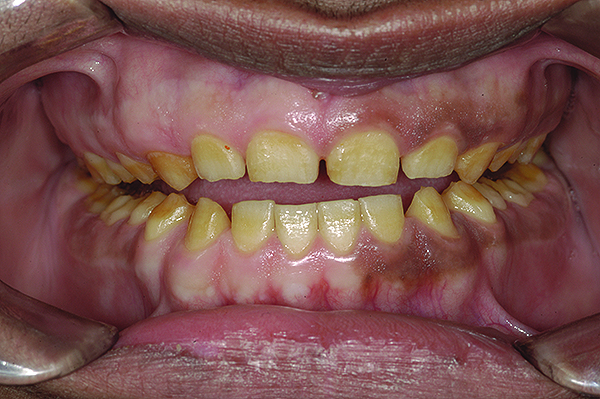

Figure 2. Preoperative 1:2 retracted frontal view.

Figure 2

The authors report on a 21-year-old patient who presented with severe discoloration and mild sensitivity of teeth (Figure 1). The teeth visible in his smile were very short, unsightly, and unbecoming for his age.

A thorough clinical examination and analysis were carried out to assess the esthetic and functional problems of the patient (Figure 2 through Figure 7). The medical history was non-contributory, except for mild leukoderma. Temporomandibular joint (TMJ) function was within normal range.